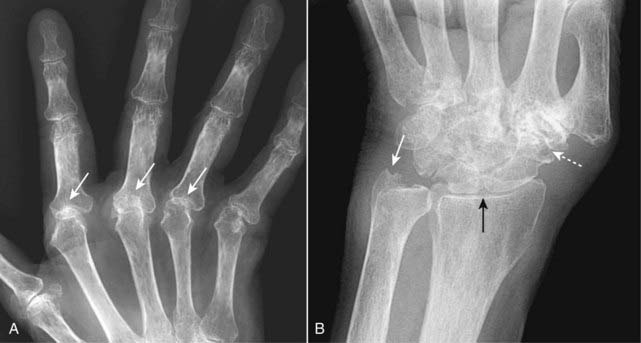

Figure 23-13 Rheumatoid arthritis, hand (A) and wrist (B).

A, In the hand, the erosions of RA tend to involve the proximal joints: the carpal-metacarpal joints, metacarpal-phalangeal (solid white arrows), and proximal interphalangeal joints. Late findings in the hands include deformities such as ulnar deviation of the fingers at the MCP joints, subluxation of the MCP joints, and ligamentous laxity leading to deformities of the fingers, which are also present in this hand. B, In the wrist, erosions of the carpals (dotted white arrow), ulnar styloid (solid white arrow), and narrowing of the radiocarpal joint space (solid black arrow) are commonly seen.